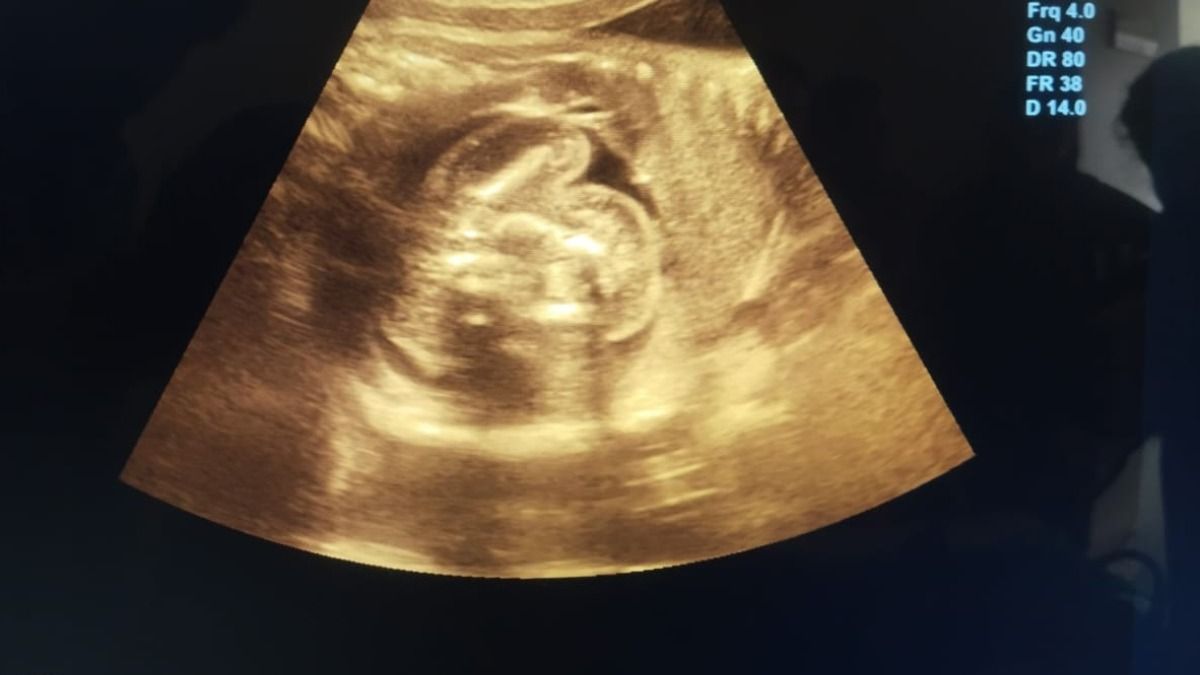

एमआरआई रिपोर्ट में पता चला की महिला प्रग्नेंट तो हैं लेकिन उसका गर्भाशय यानी यूट्रस खाली है. हैरानी की बात ये थी कि 12 हफ्ते का गर्भ उसके गर्भाशय में नहीं, बल्कि लीवर के दाहिने हिस्से में पल रहा था. गर्भ में धड़कन भी थी, यानी भ्रूण पूरी तरह से ज़िंदा था.

डॉ. गुप्ता ने आजतक को बताया, ''22 जुलाई को जब महिला इस केस को लेकर आई और जब इस एबनॉर्मल प्रेग्नेंसी का खुलासा हुआ तो हमने मेडिकल लिटरेचर खंगाला और पता चला की लीवर में भ्रूण होना बहुत ही दुर्लभ है और 14 हफ्ते से ज़्यादा इसे रखना मां के लिए जानलेवा साबित हो सकता है."